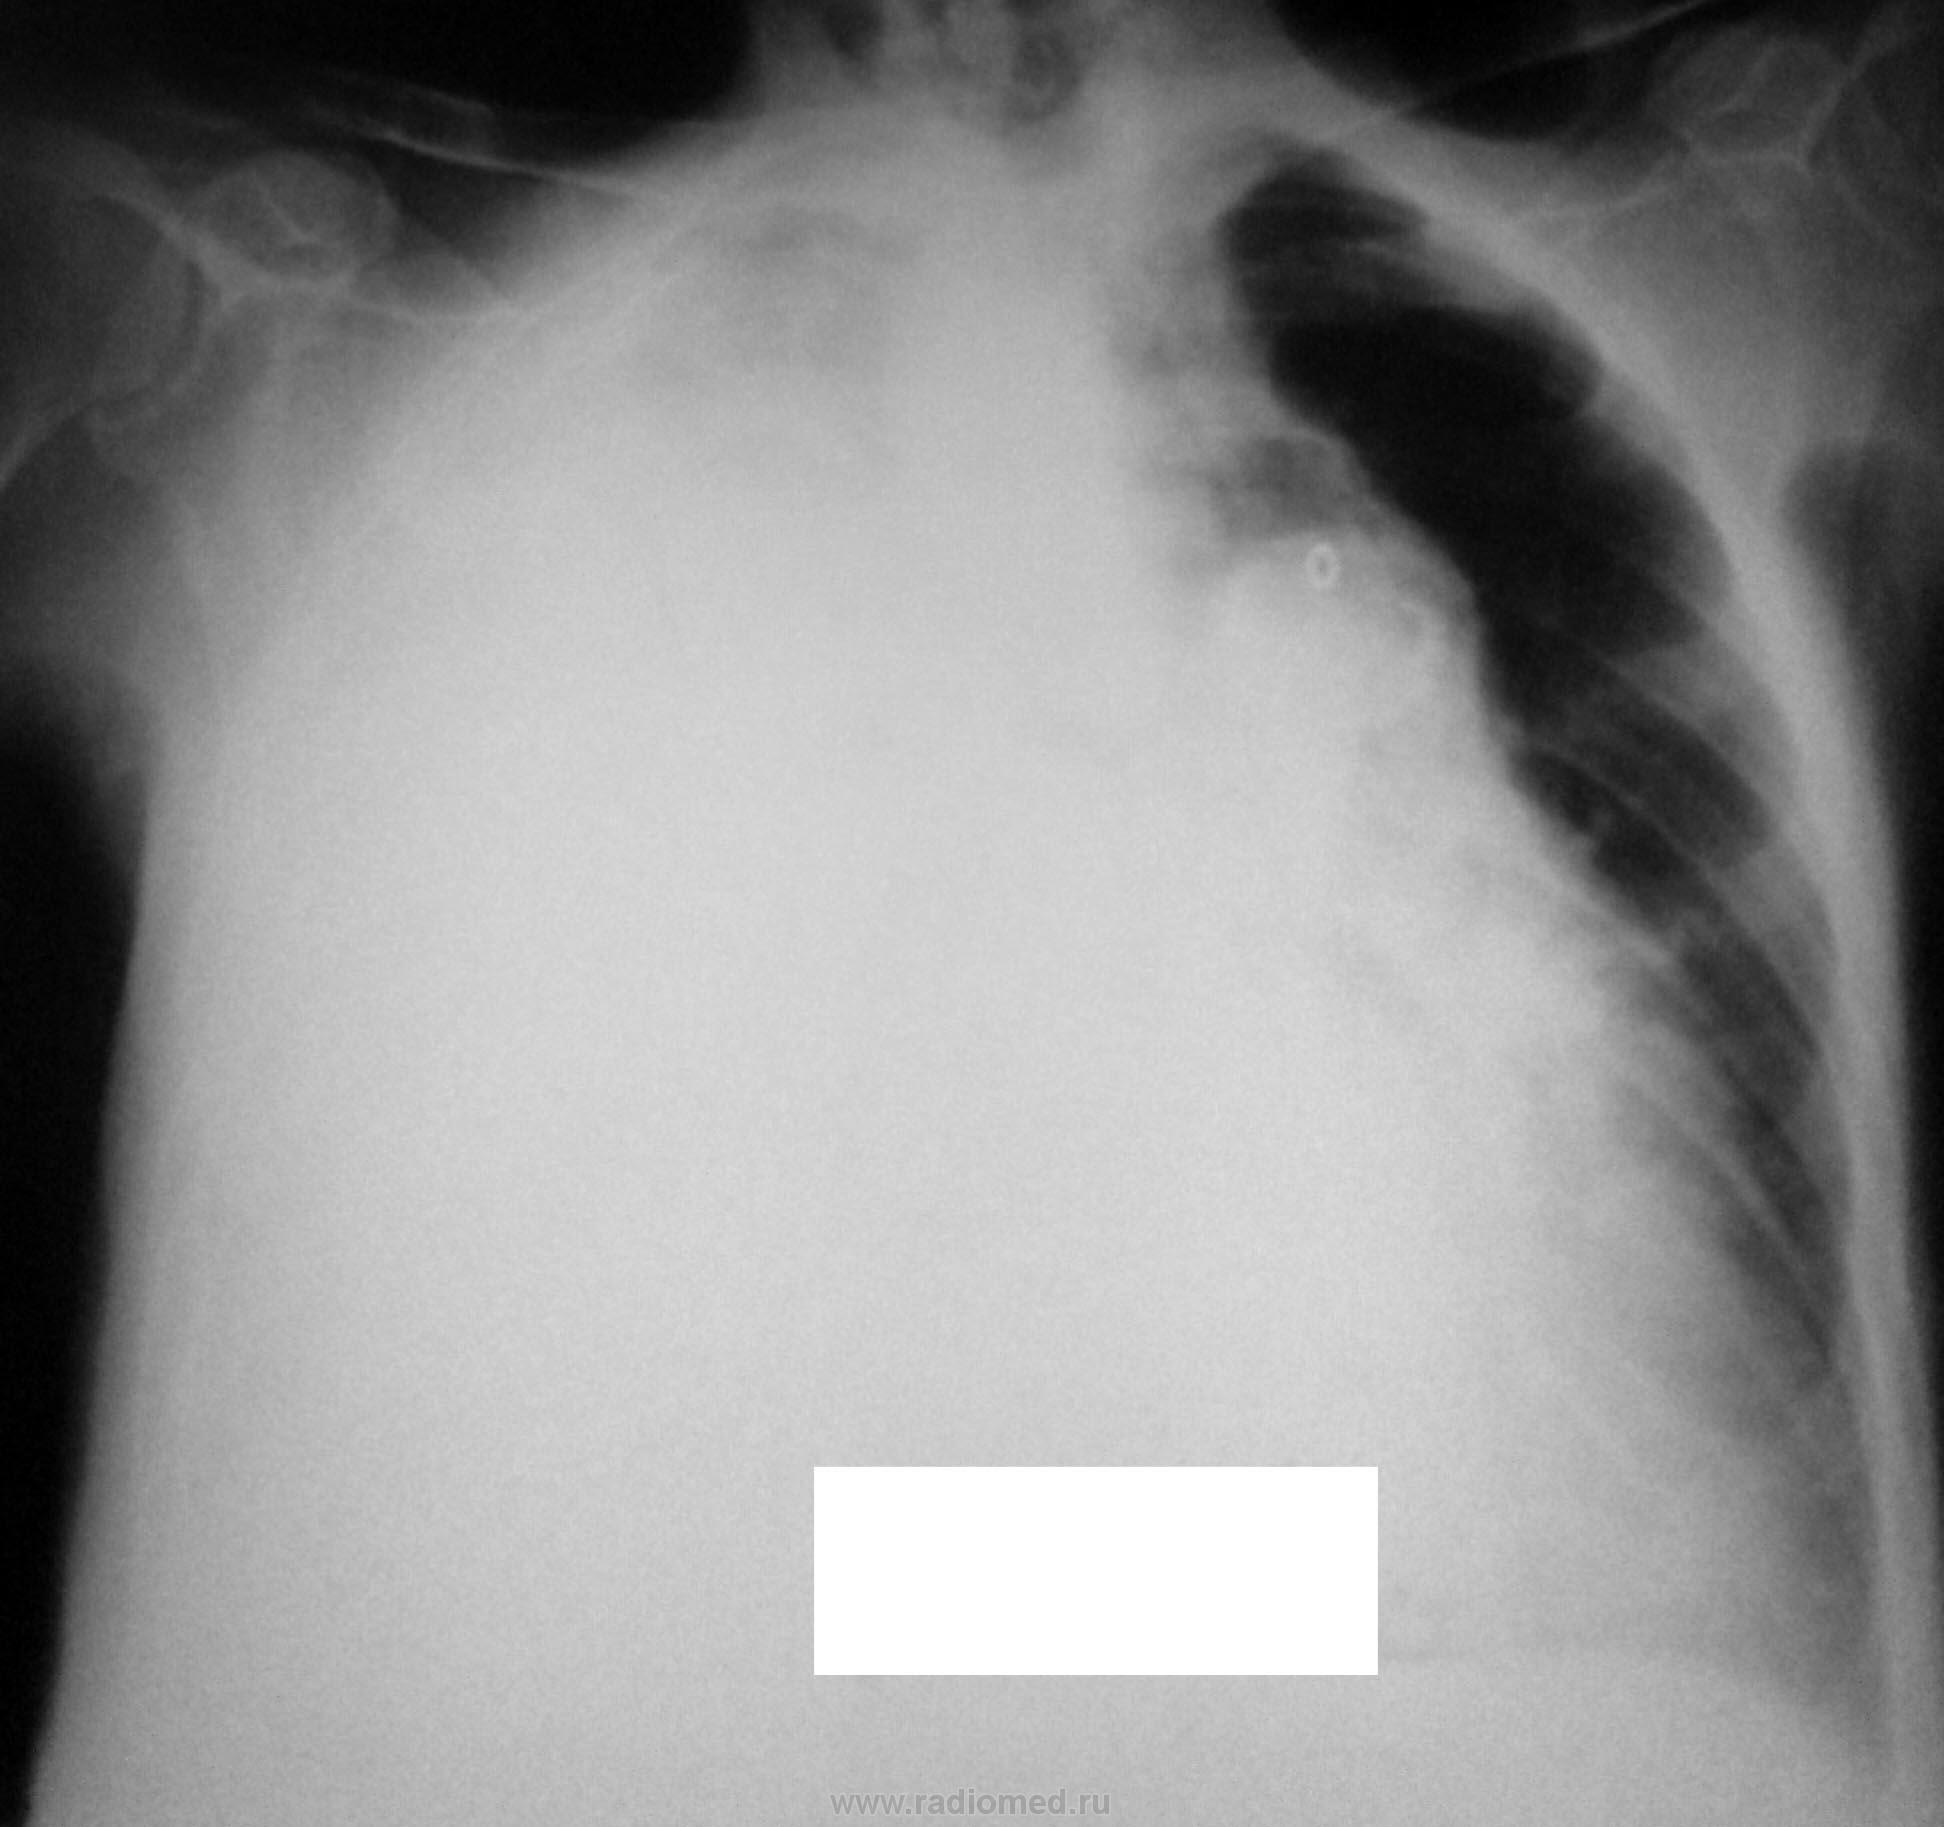

Женщина 86 лет поступила с жалобами на одышку, не лихорадит.

На рентгенограмме признаки гидроторакса справа, проведена плевральная пункция, установлен дренаж. Получено 2000 мл серозно-геморрагической жидкости.

После плевральной пункции проведено контрольное рентгенологическое обследование.

Не могу разобраться, что за уровни жидкости на рентгенограммах при контрольном исследовании, возможно жидкость между плевральными спайками? Какова природа гидроторакса? Очень интересно ваше мнение…

1. при поступлении

2. после пункции

злокачественное поражение плевры.

Присоединяюсь к предыдущим постам. Онкология.

а на боковой если посмотреть в переднем отделе огк, это что за полость. а так тоже за зло, с метестазами

Мне тоже не ясно это за полость, вопрос с образованием решен, но что за уровни жидкости?

Развитие пневмогидроторакса после плевральной пункции, на фоне спаечного процесса?

Оно самое.

Серозно-геморрагическая жидкость = c-r

Очень похоже на мезотелиому. Особенно с учётом эвакуированной жидкости.